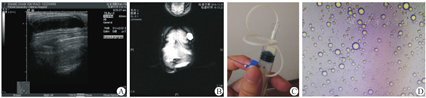

所有病例术前行MRI扫描及B型超声检查,发现乳腺囊性肿块直径为2.5~6.0 cm。B型超声提示肿块边界清楚,低回声囊性占位(图2A)。MRI显示T2高信号,内部信号均匀,与周围组织界限清楚(图2B)。另外行垂体及卵巢检查,未见明显占位。

5例患儿术前细针穿刺明确临床诊断。1例男患儿行囊肿完整切除术,4例女患儿中,2例行手术切除,2例行细针完整抽吸分泌物,随访观察。

5例患儿术前细针穿刺检查可见乳汁样分泌物(图2C),分泌物予以显微镜下观察可见脂滴样表现(图2D)。3例患儿的分泌物行乳糜试验,其中2例阳性(病例2、4),病例1阴性(表1)。3例患儿行手术切除,术中见包膜完整(图3)。术后病理检查HE染色显示囊形结构,内衬立方上皮,部分上皮细胞胞质空亮并可见顶浆分泌,局部区域可见淋巴细胞、浆细胞、嗜酸性粒细胞浸润(图4A)。其中病例4的免疫组织化学检测提示黄体酮受体(prolactin receptor,PR)表达阳性,雌激素受体(estrogen receptor, ER)表达阳性,CD34表达阳性(图4B-D)。5例患儿术后随访2~5年,均未见复发,也无其他并发症。